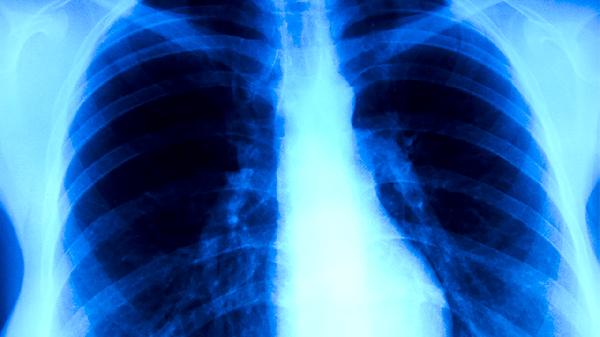

放射治疗常用于术后辅助治疗或无法手术的患者,通过高能射线破坏癌细胞。质子治疗和调强放疗能精准定位肿瘤,减少对周围组织的损伤。治疗期间可能出现结膜充血、干眼症等反应,需配合人工泪液缓解症状。